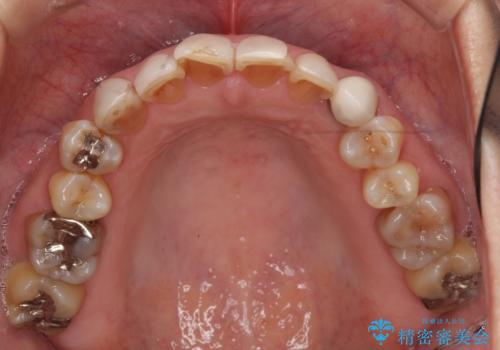

- 前歯の色や形を全体的に綺麗したいといらっしゃった方の症例です。

上顎は左側 4 番目から右側 4 番目までの 8 歯をオールセラミッククラウンで補綴しました。

下顎は左側 4 番目から右側 4 番目までの 8 歯と左下 567 ブリッジをオールセラミッククラウンで補綴し、右下67の銀歯はセラミックインレーによる修復を行いました。